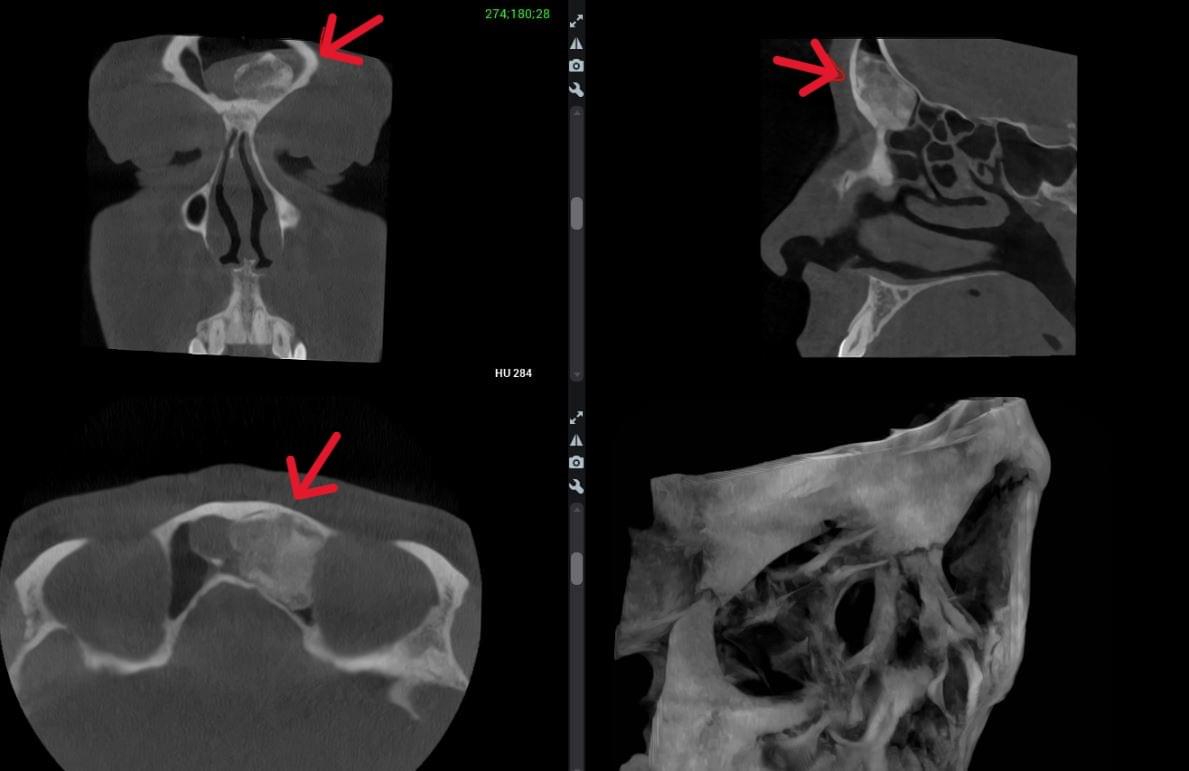

КПКТ (конусно-променева комп’ютерна томографія) — це 3D-знімок високої роздільної здатності. На відміну від звичайного рентгену, КТ показує:

Діагностика гайморових пазух за допомогою КТ

У сучасній медицині КТ придаткових пазух носа (або КТ синусів) — це «золотий стандарт»

діагностики для ЛОР-лікарів та щелепно-лицевих хірургів. Звичайний рентген часто не

показує повну картину, а МРТ не завжди доступний і дорожчий. Комп’ютерна томографія дає

детальну 3D-модель усіх пазух (гайморових, лобних, клиновидних та решітчастого

лабіринту) за 10 секунд і з мінімальною дозою опромінення.

У MyRayLab використовують сучасний апарат Planmeca 3D — доза опромінення всього 12 мкЗв (в 10–20 разів нижче, ніж у звичайних КТ), сканування 10 секунд, HD-якість.